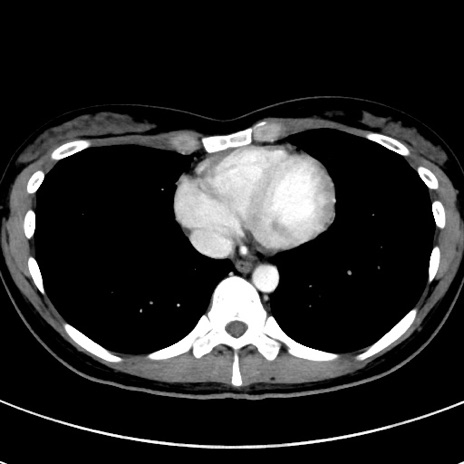

症例17(横断像)

【症例】20歳代女性

【主訴】嘔吐、下腹部痛

【現病歴】昨日夕食後に嘔吐し下腹部痛が出現。本日になっても嘔吐持続し改善しないため来院。

【身体所見】意識清明、BT 37.2℃、BP 108/67mmHg、腹部:平坦、やや硬、下腹部正中から右にかけて圧痛あり、反跳痛軽度あり、tapping pain(+)。

【データ】WBC 13600、CRP 14.94